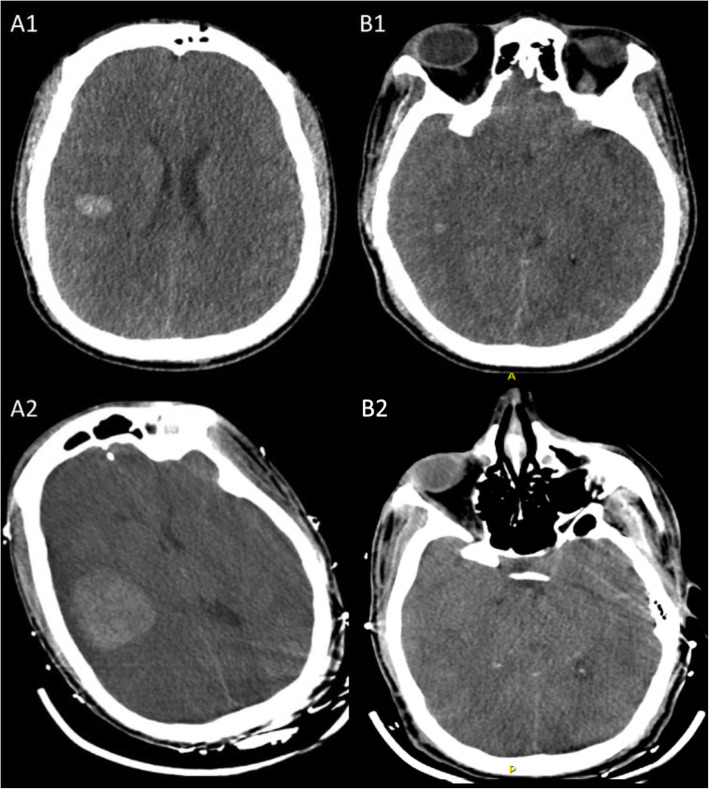

A 46-year-old African American male presented to an outside hospital with 72 h of altered mental status. Past medical history was significant for chronic myelocytic leukemia in accelerated phase on dasatinib, ulcerative colitis, polysubstance abuse (cocaine, cannabinoids, and heroin), and splenic laceration status post splenectomy. On initial examination patient was combative and disoriented but was otherwise nonfocal. Initial blood work revealed leukocytosis (43,400 cells/mm3), INR > 5, creatinine 1.74 mg/dL, and lactic acidosis (pH 7.13, anion gap 30). CT brain showed multifocal intracerebral hemorrhages (ICH) in the right frontotemporal region (Fig. 1 (A1 and B1)). He was subsequently transferred to the neurocritical care unit with a coagulation profile suggestive of disseminated intravascular coagulation (fibrinogen – undetectable, d-dimer > 35,200 ng/mL, haptoglobulin < 10 mg/dL, and activated plasma thromboplastin time of 54.5 s. He was treated with cryoglobulin, fresh frozen plasma and platelet transfusions but developed tumor lysis syndrome (TLS) with elevated uric acid (12.2 mg/L, phosphorous 6.6 mg/dL. Repeat neuroimaging 6 h from initial scan showed hematoma expansion. The patient was started on intravenous hydration, allopurinol, hydroxyurea, rasburicase, and nilotinib. He developed acute respiratory failure and was intubated. Peripheral smear confirmed myelocytic leukemia with monocytic differentiation. Given the acute ICH, he was not a candidate for intensive chemotherapy regimen but pheresis for leukoreduction was initiated. He became hypotensive requiring multiple vasopressor medications and was started on broad spectrum antibiotics. Initial EEG showed continuous generalized slowing maximal in the right hemisphere suggestive of severe encephalopathy without seizure activity. Fibrinogen improved to 125 mg/dL. Repeat CT brain scan was stable.

Fig. 1.

Computerized tomography of the brain – axial sections. A1, B1 – initial scan showing intracerebral hemorrhage in right frontal and temporal areas. The midbrain slice shows effacement of quadrigeminal cistern. A2, B2 – Day 3 scan showing large hemorrhage with intraventricular extension, severe cerebral edema with loss of grey-white differentiation, midbrain compression, and bilateral uncal herniation

He was transferred to medical intensive care unit for management of multiorgan failure and TLS. On hospital day three at 8:00 am his right pupil became dilated and non-reactive. Repeat CT brain again was immediately obtained and showed stable right frontal hemorrhage although with multiple new bilateral supratentorial hemorrhages as well as uncal herniation and midbrain compression (Fig. 2 (A2 and B2)). Although at 09:30 am the left pupil also became dilated and non-reactive, neurosurgical intervention was deferred due to coagulopathy and overall poor prognosis. Approximately 1 h prior to left pupillary dilatation, His continuous electroencephalography (cEEG) showed worsening bilateral cortical dysfunction between 8:25–8:35 am (Fig. 2a). Quantitative Electroencephalography (QEEG) showed a transition from decrease in frequencies, changes in asymmetry, decrease in amplitude, and an increase in burst suppression ratio 2 h prior to onset of burst supression (Fig. 2b-c). No EEG reactivity was noted at this time. Despite hyperventilation and hyperosmolar therapy, cerebral herniation was not reversed. Due to poor prognosis, family requested comfort measures and the patient subsequently expired.